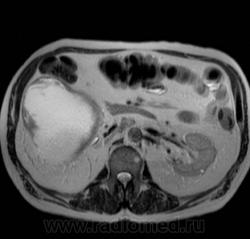

Кистозно-солидное образование н/3 правой почки, солидный компонент хоть и минимальный, но он есть, следует с ним внимательнее разобраться, я бы отнес данное кистозное образование к IV категории по Босняку.

А. эта опухоль больше похожа на "добро" или "зло"?

Добрый вечер. Босняк 4 означает что образование надо рассматривать как злокачественное, пока не будет доказано обратное или подтверждена злокачественная природа.

Сто процентный рак. Без всяких босняков.

Я бы в диф ряде рассмотрел бы эхинококкоз - в нижнем полюсе образования есть перегородка.

А вот метастазов рака почки, по видимому, не видит никто) а они есть)

Пока нет данных морфологии по этой кисте - не отказываюсь от своего мнения об эхинококке. Статьи по изолированому эхинококку почек(всего 3 процента по статистике) и других редких локализаций можно посмотреть здесь http://ifolder.ru/21262829, если кому-то еще интересна дискуссия